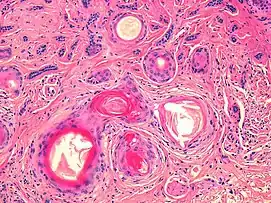

Nodular basal-cell carcinoma

Nodular basal-cell carcinoma (also known as "classic basal-cell carcinoma") accounts for 50% of all BCC.[27] It most commonly occurs on the sun-exposed areas of the head and neck.[28]: 748 [29]: 646 Histopathology shows aggregates of basaloid cells with well-defined borders, showing a peripheral palisading of cells and one or more typical clefts.[27] Such clefts are caused by shrinkage of mucin during tissue fixation and staining.[30] Central necrosis with eosinophilic, granular features may be also present, as well as mucin. The heavy aggregates of mucin determine a cystic structure. Calcification may be also present, especially in long-standing lesions.[27] Mitotic activity is usually not so evident, but a high mitotic rate may be present in more aggressive lesions.[27] Adenoidal BCC can be classified as a variant of NBCC, characterized by basaloid cells with a reticulated configuration extending into the dermis.[27]